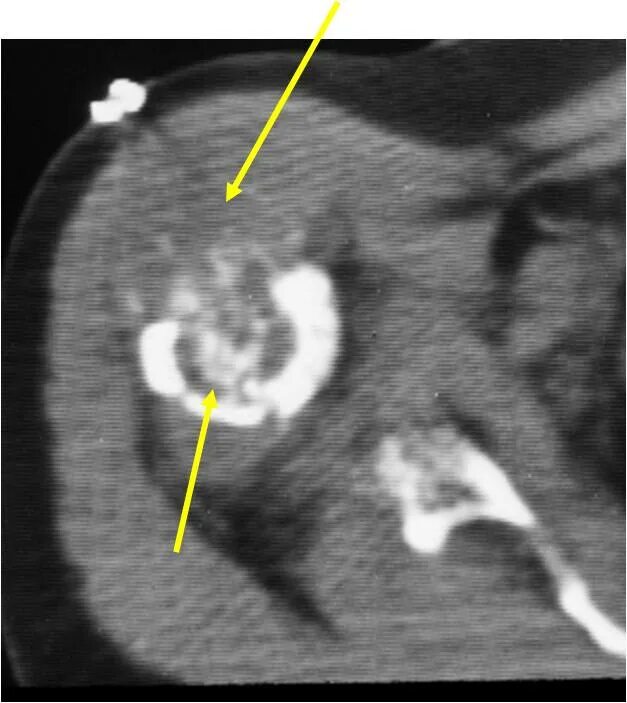

Фиброма кт